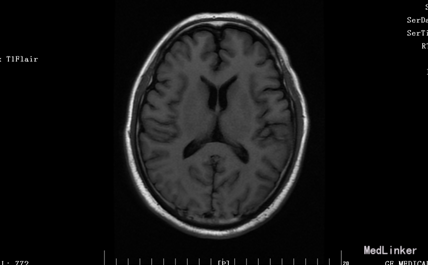

入院体检:T 36.9°C,P 87次/分,R 22次/分,BP 136/69mmHg。全身皮肤无黄染及出血点,全身浅表淋巴结未扪及肿大。双肺呼吸音清,未闻及干湿性罗音。心率87bpm,律齐,各瓣膜听诊区未闻及杂音。腹平,腹肌软,肝脾肋下未及,无压痛、反跳痛,肠鸣音正常。脊柱四肢无畸形,双下肢无水肿。神经系统:神清语晰,对答切题,记忆力、定向力、计算力正常,查体合作。双侧瞳孔等圆等大,直径约3mm,对光反射灵敏,双眼球活动自如,未见眼震。双侧额纹对称,双侧鼻唇沟对称,伸舌居中。四肢肌张力正常,左侧肢体肌力II级,指鼻试验、跟膝胫试验、闭目难立征未能配合检查。双侧腱反射对称存在,双侧巴氏征未引出。颈软,双侧克氏征、布氏征(-)。 辅助检查:生化:超敏C反应蛋白:2.6mg /l、乳酸脱氢酶(LDH):105U/L、甘油三酯(TG):2.32mmol/L、尿酸(URIC):416umol/L;同型半胱氨酸:14.3umol /l;D-二聚体定量:270ng /ml;糖化血红蛋白(HbA1c):5.1%;红细胞沉降率:3mm/h;人脂蛋白相关磷脂酶A2:378ng /ml;风湿十二项:(-); 胸部DR:主动脉硬化,双肺未见异常。心脏彩超:LVEF:66%。心内结构未见异常。 心内未见异常血流。 左室舒张功能降低。颈血管彩超:双侧颈总动脉、颈内动脉、颈外动脉、椎动脉未见异常。 双侧颈动脉、椎动脉血流速度正常。 急诊CT未见明显异常。 头颅MR:1、 双侧额叶软化灶,病灶周边少许胶质增生;2、MRA示未见明显异常。 头颅CTA:双侧颈内动脉虹吸段、双侧大脑中动脉、双侧大脑前动脉及其分支管壁尚规则,管腔通畅未见明显狭窄;右侧椎动脉颅内段管腔较左侧稍细小,余椎动脉、基底动脉及双侧大脑后动脉管腔未见明显变窄。大脑willis动脉环清晰显示,未见明显异常。 头颅CTV:大脑静脉系统上矢状窦、窦汇、横窦、乙状窦、直窦、大脑大静脉和颈内静脉管壁规则,管腔通畅未见狭窄、畸形等异常。 动态心电图示:1.窦性心动过缓;2.偶发室性早搏;3.偶发房性早搏;4.提示不完全性右束支阻滞;5.T波改变(心率快时);6.心率变异性:正常。 脑电图无异常。

患者入院时血压不高,溶栓后立即行头颅MR,未见明显病灶。但患者体征尚存在,考虑可行头颅的薄层扫描或者改变B值。另外关于栓子的来源还有疑惑,颈动脉超声没看到动脉硬化、板块,TCD结果也正常。后来再回顾病史,患者发病的过程中有感到心慌,急诊生化血钾稍低,动态心电图报有窦性心动过缓、不完全性右束支阻滞,可考虑为心源性。另患者入院时出现左手抖动、头痛症状,为刺激性症状,但MR、CTA、CTV、脑电图未见异常。也是一个疑惑的地方,希望大家给予交流指正。患者一周后出院,左侧肢体肌力几乎恢复正常。